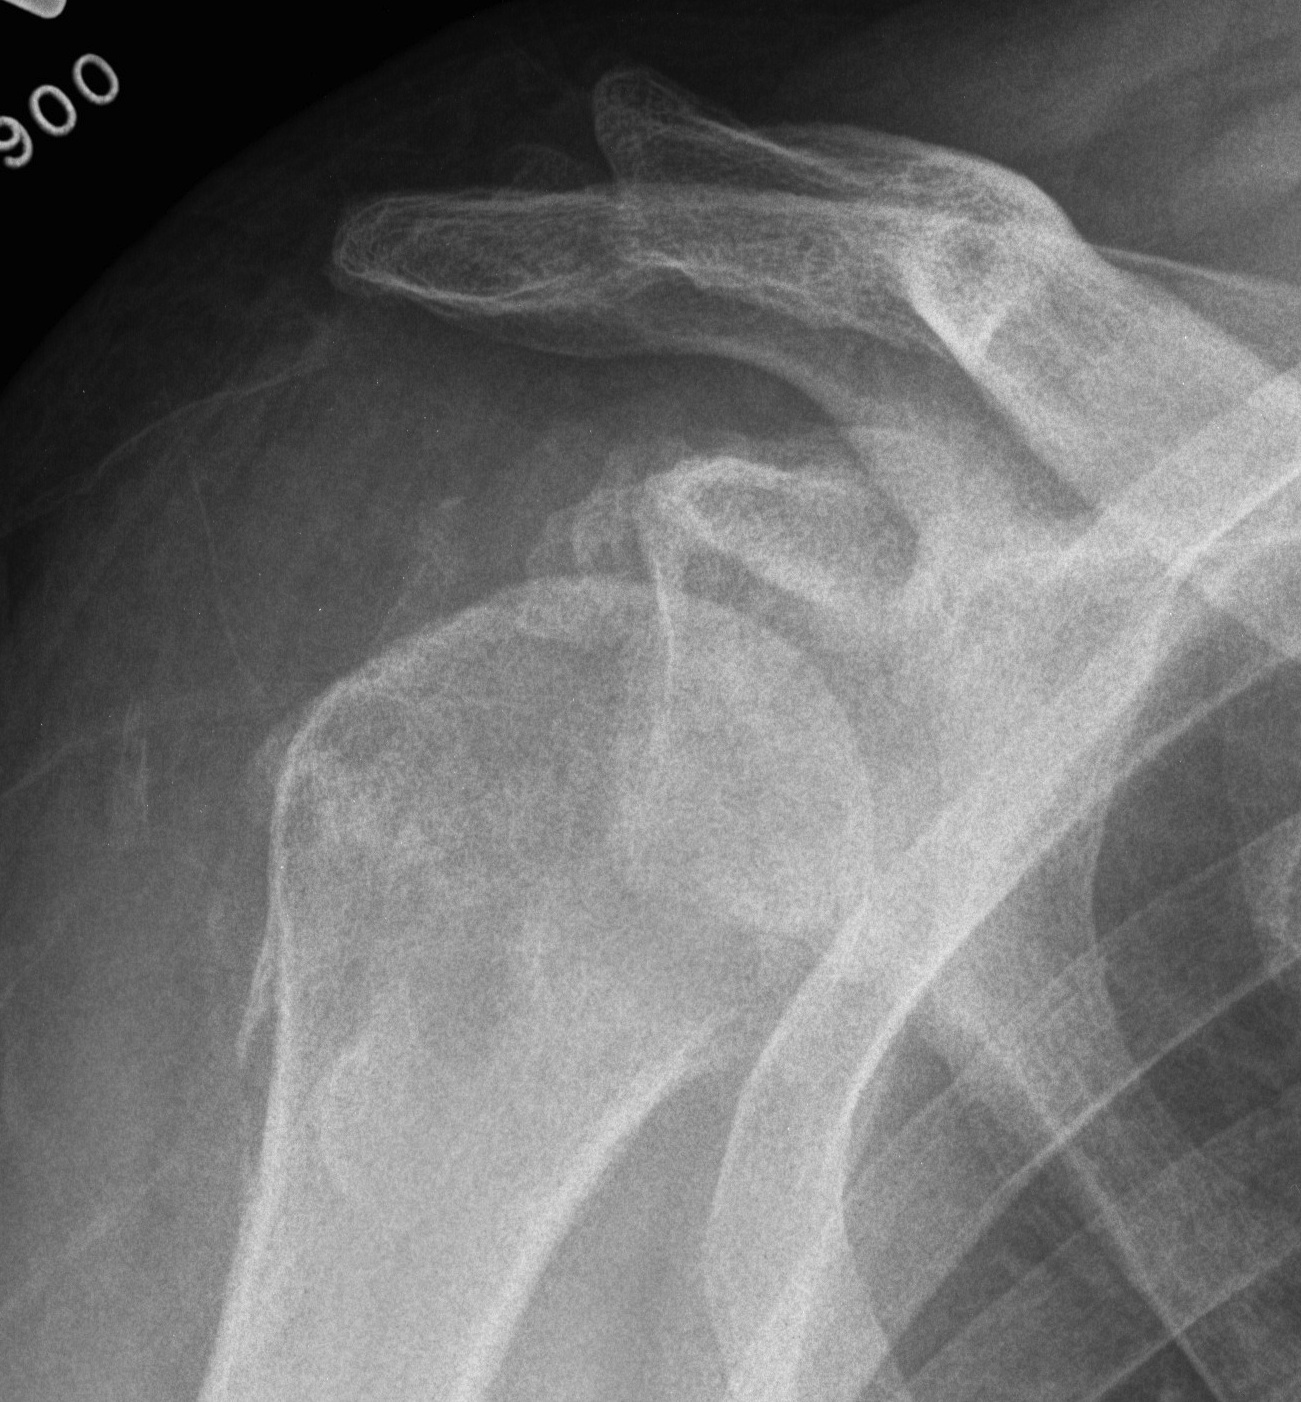

Xray

Signs of chronic shoulder dislocation

Chronic shoulder dislocation with large Hill Sachs and minimal glenoid deficiency

Chronic shoulder dislocation with large Hill Sachs and significant glenoid deficiency